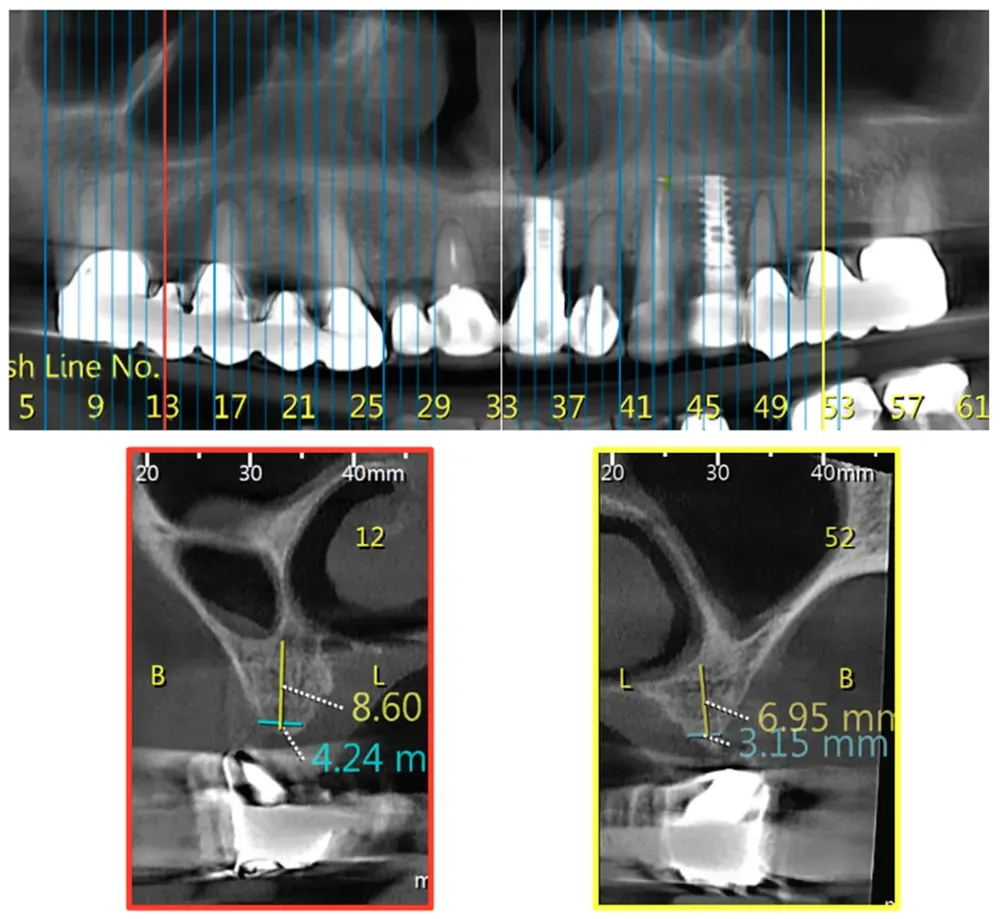

Classe 2 della variante big nose del seno mascellare

Classe 2

Classe 3 bilaterale della variante Big nose del seno mascellare

Classe 3 bilaterale